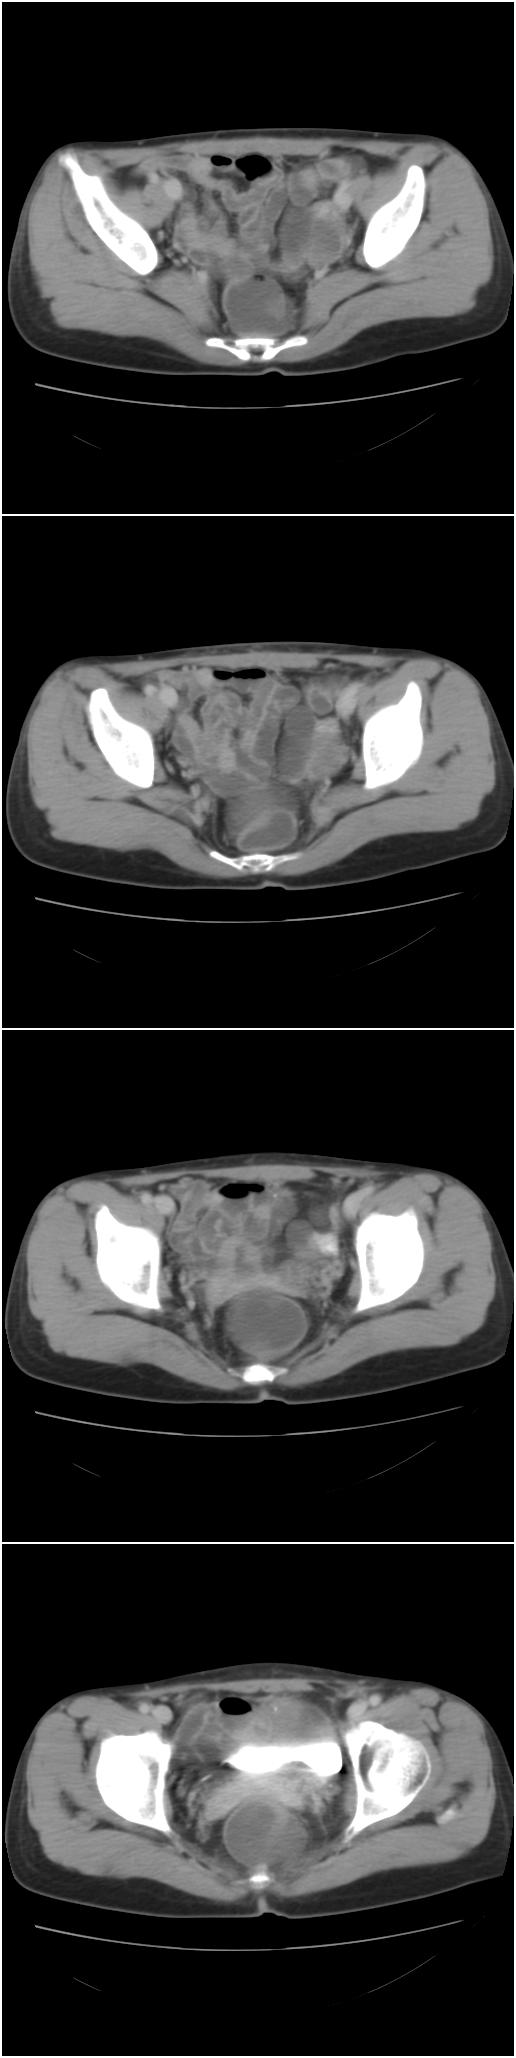

以下是今天的增强片,大家可以看看:

右髂骨见一类圆形略高密度区,似见分层,骨质破坏不明显

考虑良性病变,以动脉瘤样骨囊肿可能性大

右侧髂骨后缘囊状膨胀性骨质改变,无明显骨间隔,周围无明显硬化及骨膜反应,周围软组织无异常,相邻骨组织密度增高,考虑:动脉瘤样骨囊肿可能,要注意与骨巨细胞瘤及转移瘤鉴别。

右侧髂骨膨胀性骨质破坏区 囊内密度尚均匀 骨巨细胞瘤可能性大 动脉瘤样骨囊肿不除外 建议mr观察囊内成分明确诊断 左侧附件区包裹性积液

该病人今天做了增强,右侧髂骨病灶明显强化。

右侧髂后上棘局限性囊状骨质破坏,大部分界清,似见轻度硬化边,内无分格及钙化,病灶上部局部显示模糊。考虑;骨巨细胞瘤可能大,不除外abc。另可见子宫肌瘤术后子宫缺如。

临床和影像学表现:女性患者46岁,有子宫肌瘤手术病史。影像所见可见残余宫颈部分,左右附件未见新生物;右髂骨翼后端囊状膨胀性骨破坏,囊性部分感觉有强化(楼主标上增强前后的ct值就很好了),未见明确的液—液平面,周边硬化不明显或轻度硬化。

分析:患者年龄46岁,没有明确外伤病史,病变呈膨胀性骨破坏,囊性部分未见明确的液—液平面,周边硬化不明显。综合分析该病例比较符合骨巨细胞瘤,不太符合动脉瘤样骨囊肿。

诊断:1、首先考虑骨巨细胞瘤;2子宫肌瘤术后改变